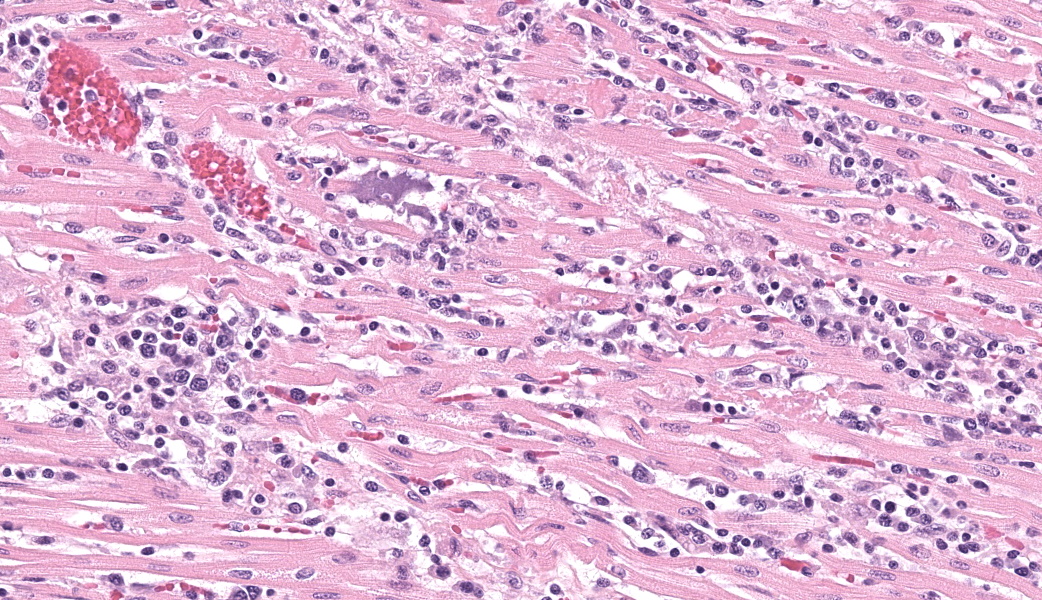

Expanding and infiltrating all layers of the heart, with the greatest severity in the myocardium, are large numbers of plasma cells, lymphocytes, and macrophages. Cardiomyocytes in areas of inflammation are multifocally hypereosinophilic, shrunken, and have striation loss with fragmented to absent nuclei (necrosis). There is mild, multifocal, interstitial fibrosis often associated with cardiomyocyte degeneration and inflammation. Throughout the myocardium, there are occasional cardiomyocytes that contain intrasarcoplasmic, variably sized (up to 100 μm in length) pseudocysts with numerous, 2-3 μm, round protozoal amastigotes.Contributor's Morphologic Diagnoses:

Heart: Severe, multifocal, chronic-active, lymphoplasmacytic and histiocytic pancarditis with intrasarcoplasmic pseudocysts containing amastigotesContributor's Comment:

T. cruzi can infect myocytes, endothelial cells, fibroblasts, and adipocytes, but has a tropism for cardiac muscle tissue.11 Grossly, there are no pathognomonic lesions for Chagas disease. Histologically, the cardiomyocytes will be expanded by a pseudocyst containing amastigotes. While best observed ultramicroscopically, the amastigotes will have a large nucleus and an adjacent rod-shaped kinetoplast, like Leishmania spp. Unlike the defined perpendicular orientation of the kinetoplast in Leishmania, the location of the kinetoplast relative to the nucleus changes during the life cycle and cannot be a diagnostic feature in Chagas disease.10 Unfortunately, additional diagnostics including PCR, culture, and serology were not performed so leishmaniasis cannot be completely ruled out, but the geographic and anatomic location of the organism along with the histologic appearance is most likely consistent with T. cruzi. Infection results in marked inflammation of the heart, often not associated with the intracellular pseudocysts. Myocarditis can lead to heart failure with cardiac arrest and potentially fatal arrhythmias. In this case, there was multi-organ evidence of heart failure including ascites (abdominal effusion) and centrilobular hepatocyte necrosis due to hypoxia.

Heart: Pancarditis, lymphoplasmacytic and histiocytic, subacute, multifocal to coalescing, marked, with numerous sarcoplasmic amastigotes.JPC Comment: